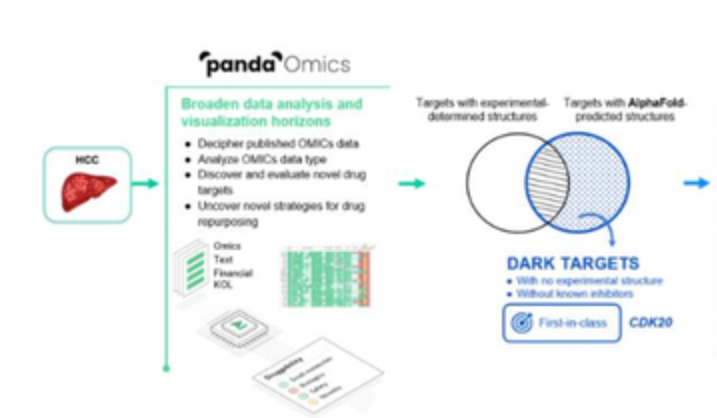

MIT把AI的预测能力又推进了一步,直接通过氨基酸序列预测蛋白质分子的生物学功能,跳过AlphaFold预测蛋白质立体结构的步骤。